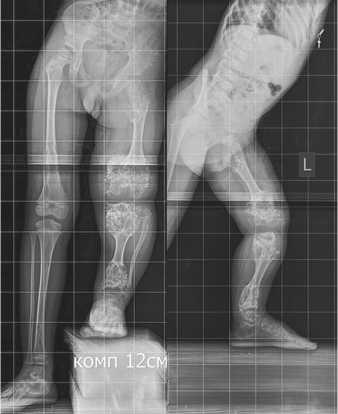

Хондроматозные очаги располагались в области проксимальных и дистальных отделов бедренной и берцовых костей, затрагивая эпиметафизарные зоны и представляя собой утолщенные отделы костей с типичным нарушением минерализации и чередованием участком минерализации и рентгенпрозрачных включений (рис. 1). Функциональные ограничения отражались в снижении способности ходьбы, необходимости посторонней помощи и использовании обуви с большой компенсацией укорочения левой нижней конечности.

Рис. 1. Рентгенограммы нижних конечностей при поступлении